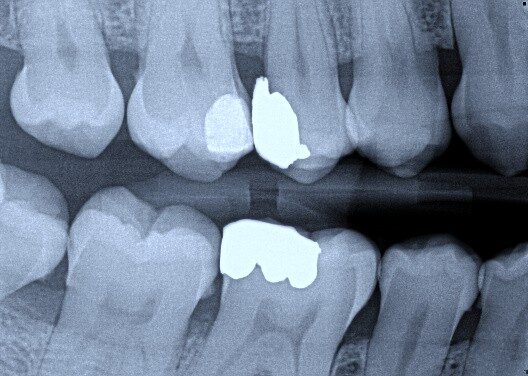

The radiograph shows evidence of

Which of the following is/are seen in the radiograph?

Which of the following is/are seen in the radiograph for tooth 3.6?

Which of the following is/are seen in the radiograph for tooth 3.7?